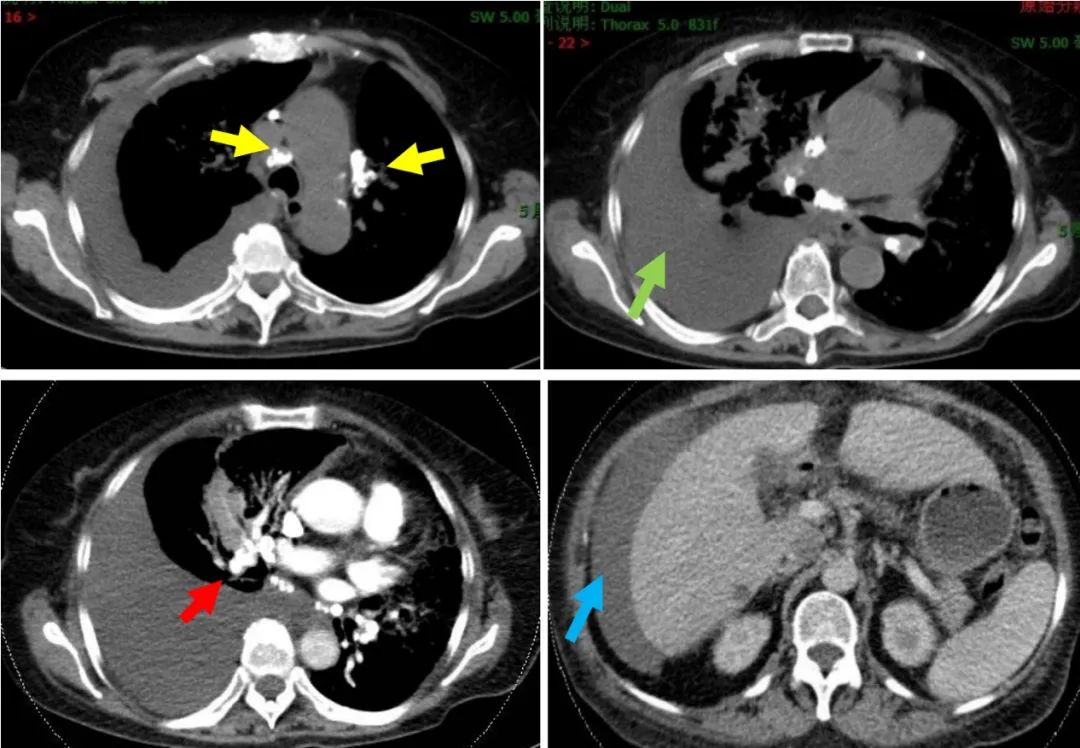

胸部增强CT(2017-02-14):双肺内多发斑片影、蜂窝状影及结节影,伴双肺气管、支气管壁稍增厚,考虑炎症,建议治疗后复查。右侧胸膜腔大量积液。右肺中下叶压迫性肺不张。纵隔及双肺门多发淋巴结钙化。胸主动脉及双侧冠脉钙化。腹水。CTPA:右肺下叶肺动脉未见明显显影,左肺下叶肺动脉显影较差。余肺动脉未见明显充盈缺损。

图2:胸部CT(2017-02-14)纵隔窗:黄色箭头示:纵隔及双肺门多发淋巴结钙化;橙色箭头示:右侧大量胸腔积液,红色剪头示:CTPA右肺下叶肺动脉未见明显显影,蓝色剪头示:肝周见腹水。